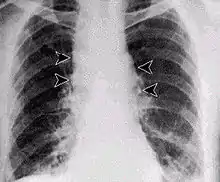

Inhalational anthrax, mediastinal widening

The spores of anthrax are able to survive in harsh conditions for decades or even centuries.[38] Such spores can be found on all continents, including Antarctica.[39] Disturbed grave sites of infected animals have been known to cause infection after 70 years.[40] In one such event, a young boy died from gastrointestinal anthrax due to the thawing of reindeer corpses from 75 years ago.[41] Anthrax spores traveled though groundwater used for drinking and caused tens of people to be hospitalized, largely children.[41] Occupational exposure to infected animals or their products (such as skin, wool, and meat) is the usual pathway of exposure for humans.[42] Workers who are exposed to dead animals and animal products are at the highest risk, especially in countries where anthrax is more common.[42] Anthrax in livestock grazing on open range where they mix with wild animals still occasionally occurs in the United States and elsewhere.[42]